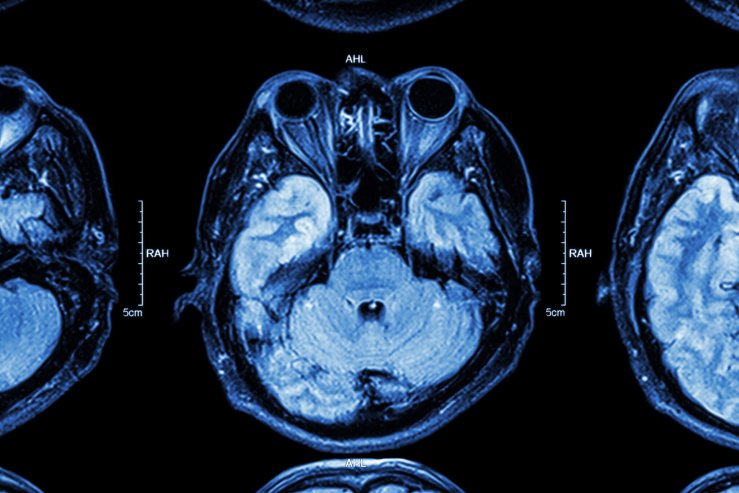

Відділення церебральної нейрохірургії — це провідний центр лікування патологій головного мозку, де проводяться високоточні мікрохірургічні, ендоскопічні та реконструктивні операції. Щороку тут проходять лікування понад 1400 пацієнтів із пухлинами, наслідками травм, гідроцефалією, аневризмами та невралгіями.

Операційні оснащені найсучаснішою апаратурою — мікроскопами Carl Zeiss, нейронавігаційними системами, ендоскопічними комплексами Stryker і Aesculap, ультразвуковими відсмоктувачами Soring та нейромоніторингом Medtronic (США). Це дозволяє працювати з мікронною точністю, зберігаючи найважливіші функції мозку і мінімізуючи ризики.

Основні напрями роботи включають:

- Видалення пухлин головного мозку — внутрішньомозкових, позамозкових, пухлин гіпофіза та задньої черепної ямки з використанням ендоскопічних і навігаційних технологій;

- Хірургію черепно-мозкової травми — усунення гематом, відновлення черепа індивідуальними титановими імплантатами;

- Лікворошунтуючі операції при гідроцефалії із застосуванням програмованих шунтів;

- Відновлення при ліквореї після травм основи черепа;

- Малоінвазивні втручання при невралгіях і компресії периферичних нервів.